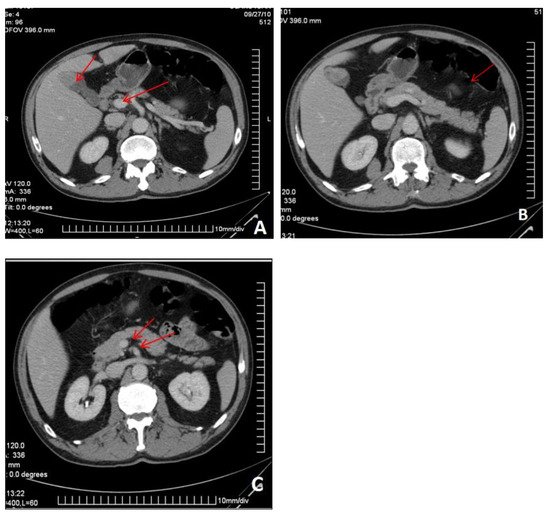

Metastatic melanoma is one of the most common malignancies associated with the spread of the primary tumor. The primary site is usually the skin or the eyes. The most frequent site of metastases is the gastrointestinal tract, accounting for 60% of cases at [...] Read more.

Metastatic melanoma is one of the most common malignancies associated with the spread of the primary tumor. The primary site is usually the skin or the eyes. The most frequent site of metastases is the gastrointestinal tract, accounting for 60% of cases at autopsy. In 2% of patients, metastases occur without a detectable primary tumor. We present a rare case of upper digestive bleeding caused by multiple gastrointestinal tract metastases from an amelanotic melanoma. This case report describes a 65-year-old male who arrived at the emergency department after experiencing an episode of upper gastrointestinal bleeding (melena). One week prior to admission, he had been treated with nonsteroidal anti-inflammatory drugs for lower back pain due to L4–L5 disc herniation. Upper digestive endoscopy revealed multiple polypoid masses in the stomach and duodenum, and capsule endoscopy showed additional lesions in the small bowel. Histopathological examination confirmed the diagnosis: metastases from an amelanotic malignant melanoma. Abdominal and cranial computed tomography scans revealed multiple secondary lesions in the brain, gallbladder, retroperitoneal area, gastrointestinal tract, and peritoneum. Localized radiotherapy was applied to the cerebral metastasis, and systemic chemotherapy with dacarbazine was initiated, resulting in a partial clinical response. Unfortunately, the disease progressed, and the patient died one month after diagnosis. Metastatic melanoma of the gastrointestinal tract is an exceedingly rare cause of upper digestive bleeding. Full article